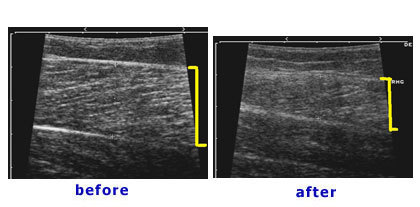

上圖例內腓相當的肥大,但外腓及比目魚肌卻很正常,病人只希望將肥大的內腓做處理。將內腓肌肉做部份切除後三個月,小腿外形得到相當大的改善。超音波檢查看出術前的內腓厚度是16mm,術後厚度是11mm,5mm的厚度改變可以有效改變外形,但不會影響小腿功能。